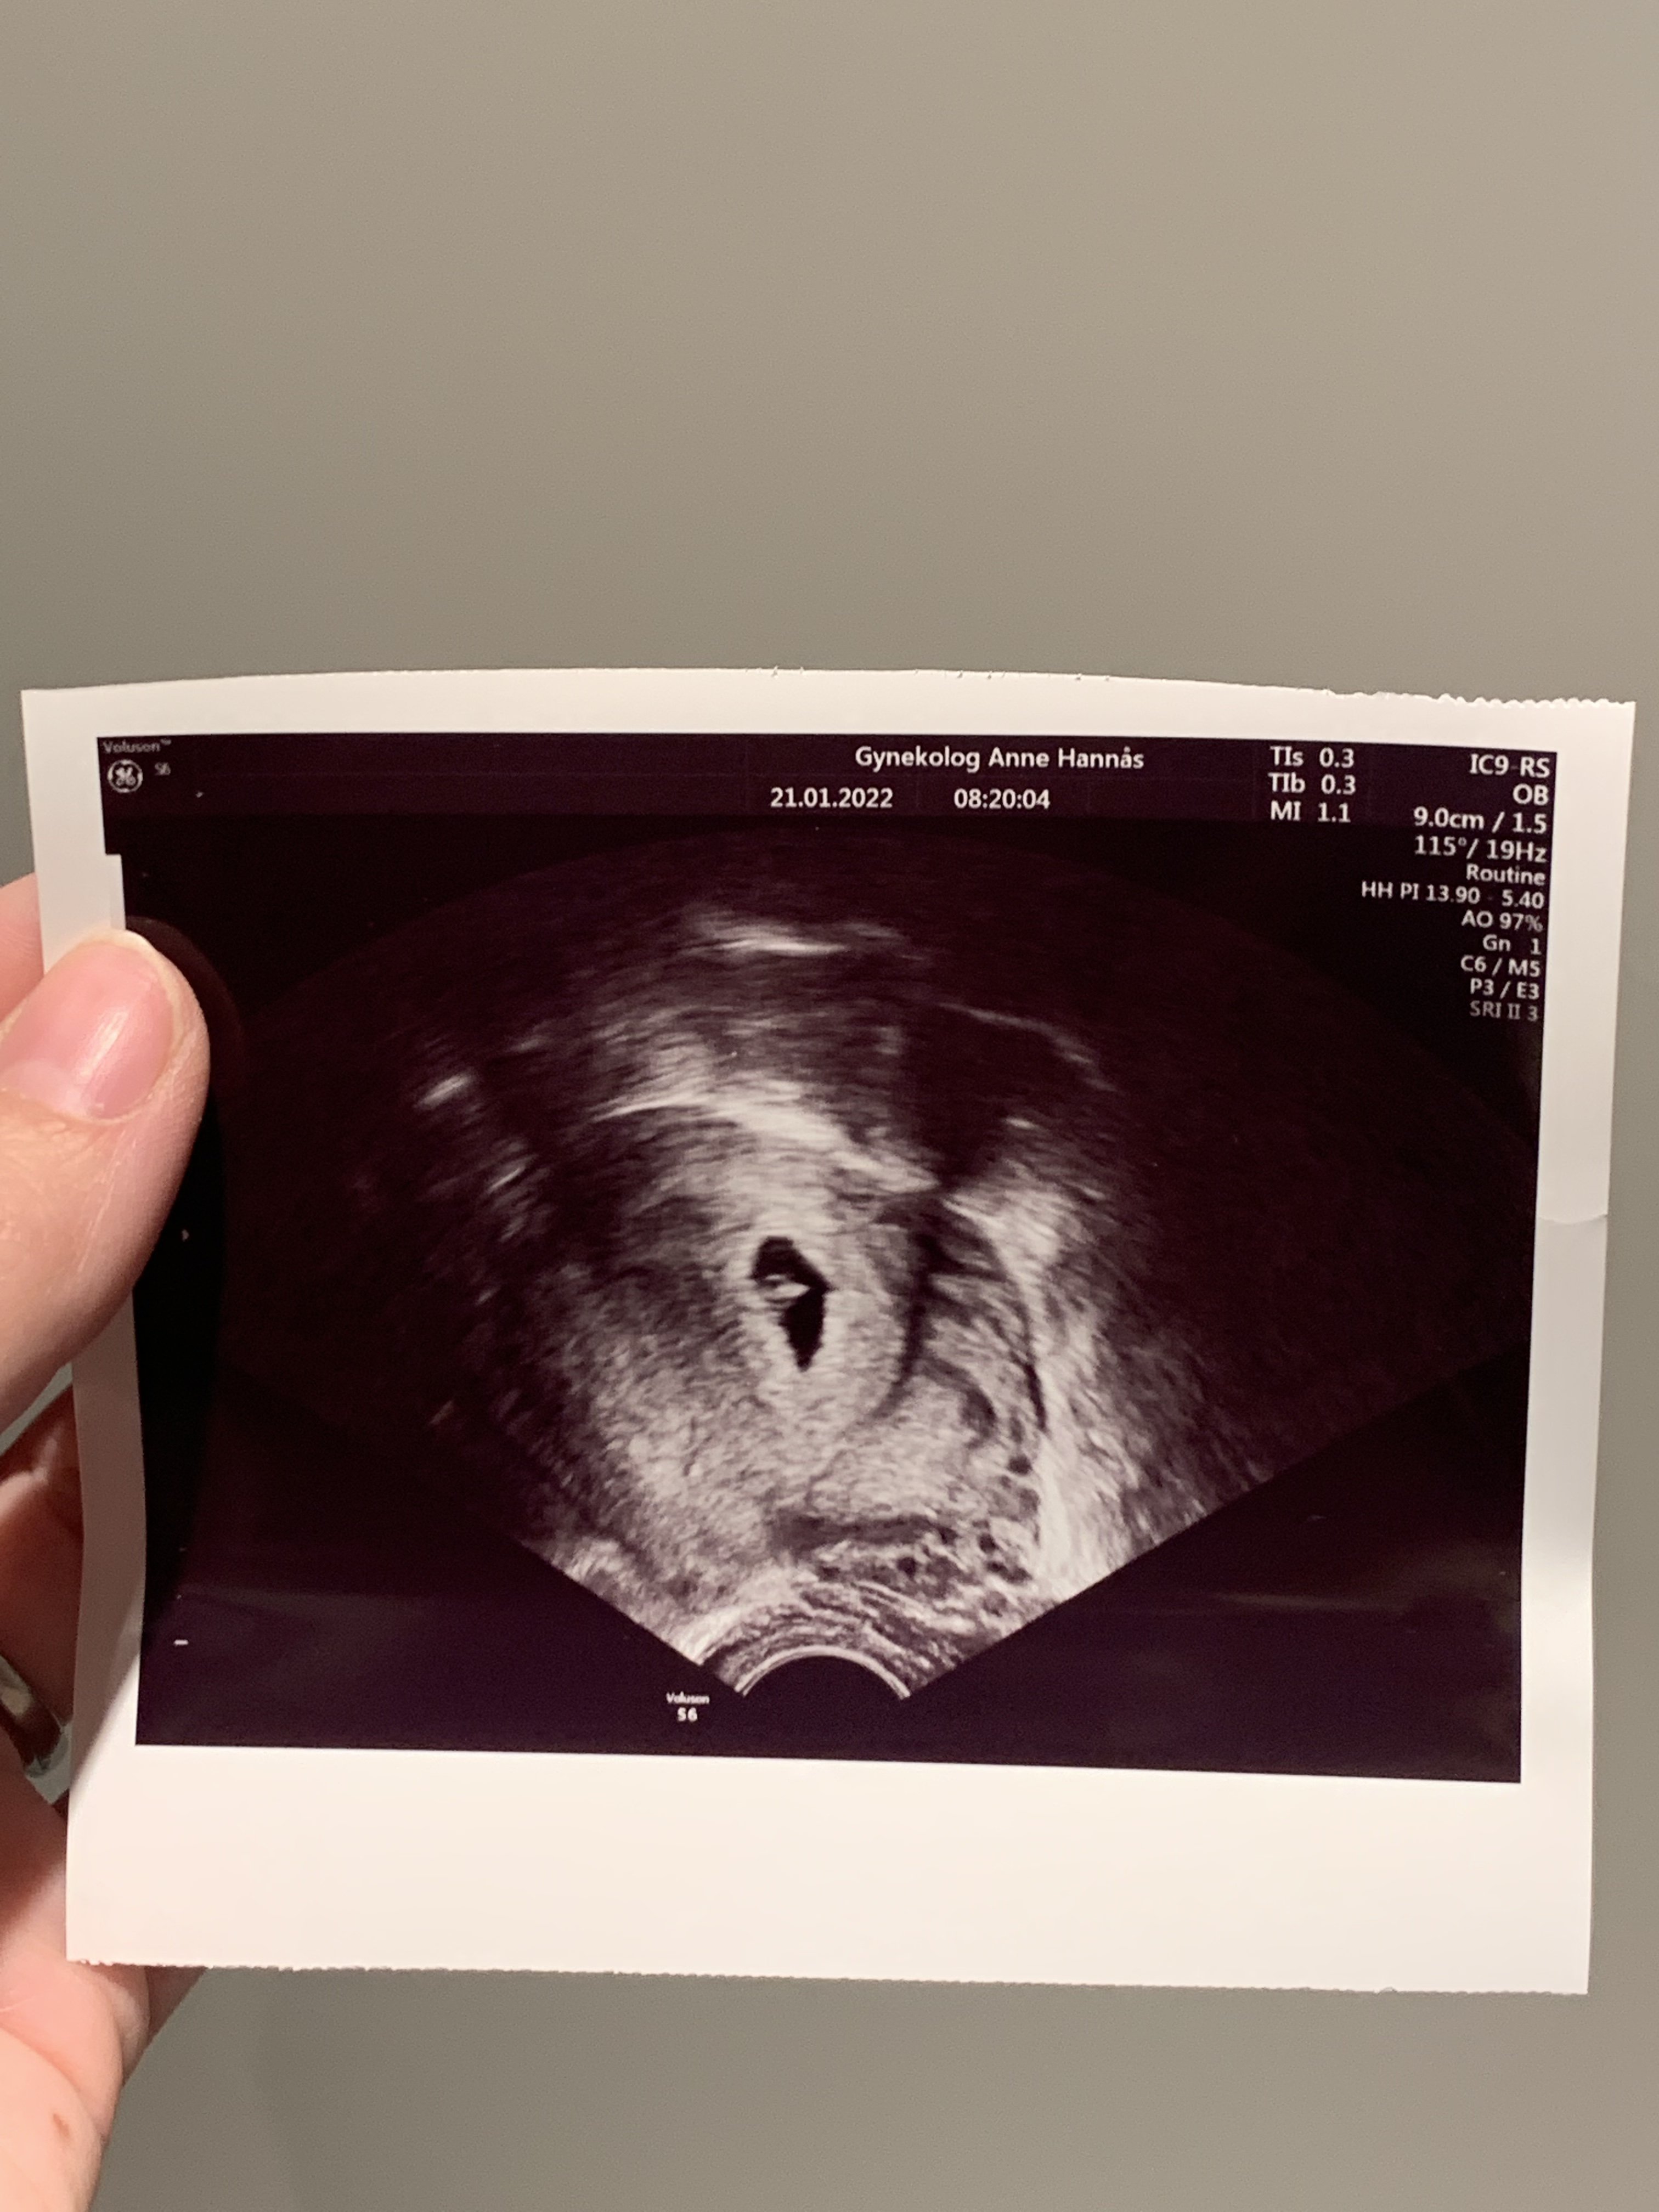

5+4

Titter bare innom for å si at jeg skal på TUL i morgen. Skulle egentlig i starten av februar men måtte avlyse timen, og siden gynekologen hadde så full kalenderen lurte hun på om jeg ikke ville komme i morgen siden da hadde hun fått en avbestilling. Antar at det ikke er så altfor mye å se, men håper jeg ser en «liten forlovelsesring». Finner trolig også ut av hvilken livmor det er snakk om og om det er flere der inne. Håper jeg får se hjertet slå også, men er forberedt på at det kan være for tidlig, og skal prøve å ikke bli redd hvis man ikke ser det.